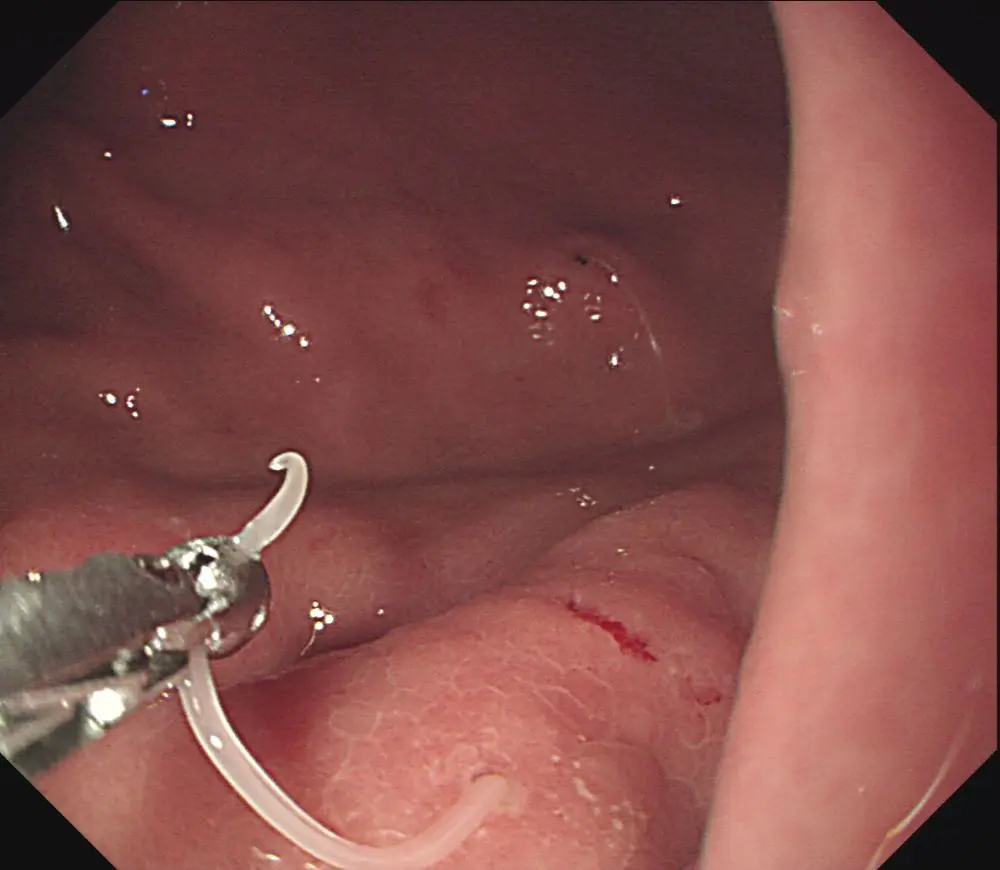

1764259885253.webp-(30494 B)

30494 B

>一度胃に入ったらどうやって駆除するの?

胃カメラで取り除く